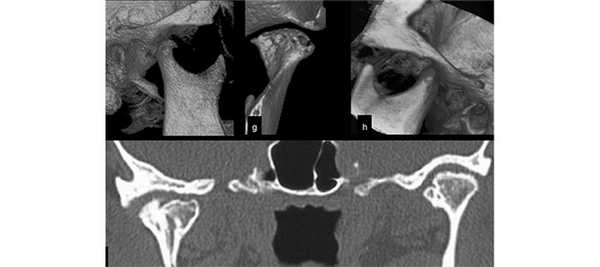

(Слева) На КЛКТ (объемный рендеринг) у пациента 15 лет определяется перелом мыщелка со смещением, полученный в перинатальном периоде. Проксимальный сегмент смещен кпереди и в этом положении сращен с ветвью.

(Справа) На КЛКТ (объемный рендеринг, вид спереди) у этого же пациента определяется асимметрия нижней челюсти. Правая ветвь в смещена кнутри, правый угол приподнят, как и окклюзионная плоскость справа. Костная срединная линия нижней челюсти смещена вправо. (Слева) На панорамной реформатированной КЛКТ нижней челюсти справа у этого же пациента определяется переднее смещение мыщелкового отростка. Кортикальная пластинка мыщелка пересекает ветвь. Угол между мыщелком и венечным отростком острый. Определяется переднее отклонение задней поверхности ветви и мыщелкового отростка.

(Справа) На панорамной реформатированной КЛКТ нижней челюсти слева у этого же пациента смещение мыщелка в отсутствует. Кортикальная пластинка мыщелка не пересекает ветвь; сигмовидная вырезка широкая, имеет ровные края.

(Слева) На косой сагиттальной КЛКТ правого ВНЧС у этого же пациента визуализируется смещенный кпереди мыщелковый отросток возле основания черепа. Суставное возвышение не сформировано. Суставное возвышение начинает формироваться с рождения под воздействием правильно расположенного и функционирующего мыщелка. Отсутствие суставного возвышения свидетельствует о раннем повреждении мыщелка.

(Справа) На косой сагиттальной КЛКТ левого ВНЧС у этого же пациента не определяется патологических изменений со стороны мыщелка, суставной ямки, суставного возвышения. (Слева) На панорамной реформатированной КЛКТ (объемный рендеринг) определяется сложный перелом нижней челюсти: вертикальный перелом правой ветви и подмыщелковый перелом с переходом на ветвь.

(Справа) На панорамной рефор матированной КЛКТ (объемный рендеринг) слева у этого же пациента определяется косой перелом ветви и венечного отростка. Двухсторонние или множественные переломы нижней челюсти встречаются редко. (Слева) На парасагиттальной КЛКТ у этого же пациента визуализируется мыщелок кв занимающий передне-нижнее положение в суставной ямке. Определяется перелом (деформация в виде «ступеньки») между проксимальным и дистальным сегментами.

(Справа) На косой сагиттальной КЛКТ левого ВНЧС у этого же пациента визуализируется маленький (вследствие имевшегося до травмы стабильного дегенеративного заболевания) мыщелок низко расположенный в суставной ямке. (Слева) На панорамной реформатированной КЛКТ у пациента с травмой лица справа определяется перелом венечного отростка, подмыщелковый перелом, а также перелом передних отделов нижней челюсти с наличием пластины.

(Справа) На панорамной реформатированной КЛКТ у этого же пациента отсутствуют травматические изменения ВНЧС. Определяются дегенеративные изменения, в т.ч. склероз и конгруэнтное уплощение суставною возвышения и мыщелка.

(Слева) На косой сагиттальной реформатированной КЛКТ определяется оскольчатый подмыщелковый перелом правого ВНЧС. Мыщелок в суставной ямке смещен кзади, переднее суставное пространство расширено. Также определяется перелом венечного отростка.

(Справа) На косой корональной КЛКТ у этого же пациента определяется оскольчатый подмыщелковый перелом. Нижний край проксимального сегмента заходит за край дистального, образуя «ступеньку». Визуализируется формирующаяся костная «мозоль», что свидетельствует об активном процессе заживления. (Слева) На панорамной реформатированной КЛКТ у взрослого пациента, получившего травму правой парасимфизеальной области (вектор приложения силы направлен от задних отделов к передним), с основной жалобой на боль в левом ВНЧС, визуализируется нормальный правый мыщелковый отросток. Не нарушено пространственное отношение мыщелка и суставной ямки.

(Справа) На панорамной реформатированной КЛКТ нижней челюсти слева у этого же пациента переломы нижней челюсти не выявлены. Пространственные отношения мыщелка/суставной ямки слева определяются хуже. (Слева) На косой сагиттальной КЛКТ левого ВНЧС у этого же пациента определяется перелом крыши суставной ямки с наличием нескольких костных фрагментов. Обратите внимание на субхондральный склероз передне-верхней поверхности мыщелка и эрозию задней поверх-ности.

(Справа) На косой корональной КЛКТ левого ВНЧС у этого же пациента определяется дефект крыши суставной ямки, подозрительный на перелом.